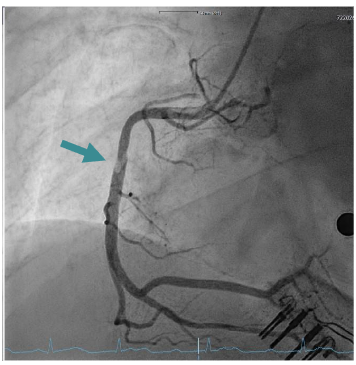

A 27-year-old patient presented with suspected ST-segment elevation myocardial infarction (STEMI). Approximately one hour prior to admission, the patient experienced onset of typical angina pectoris with accompanying vegetative symptoms (nausea and vomiting). Similar episodes had not occurred before. The patient’s medical history revealed regular or daily consumption of high-percentage alcohol, nicotine and cannabis. A few days before the event, the patient intended to consume nasal amphetamines, but due to a mix-up the substance consumed was heroin. No further substance use was reported. Furthermore, the patient had a tick bite approximately 10 years ago. The initial electrocardiogram (ECG) showed ST segment elevations in leads II, III, and avF, as well as a second-degree atrioventricular block (Mobitz type II) with a heart rate of approximately 70 beats/minute. Laboratory tests showed elevated cardiac biomarkers, with (troponin I 14.037 µg/l (cut-off value <0.045 µg/l) and CK-MB at 79 U/l (cut-off value <24U/l). Furthermore, the patient exhibited a flamboyant exanthema in large areas of the face with known atopic dermatitis. The patient reported of a pronounced stress response triggered by various problems in the work environment and social circle. After findings were reviewed in the Chest Pain Unit, based on the initial assessment, the patient was immediately transferred to the catheterization lab. The attending physician administered prehospital medication with aspirin and heparin. An emergency coronary angiography was performed, which revealed a single-vessel coronary disease with a subtotal occlusion of the right coronary artery (RCA) and high thrombus burden. During the procedure, the patient admitted that he had smoked marijuana the same morning. A primary stenting using a drug eluting stent (DES, Promus 4.0/32mm, Boston Scientific, Marlborough, Massachusetts) was performed, followed by stent optimization with balloon angioplasty. Complete reperfusion was documented immediately without evidence of remaining dissection or vascular injury. The placement of a temporary pacemaker was not necessary and the patient was transferred to our intensive care unit. Post-interventional follow-up showed no evidence of atrioventricular block and complete ST resolution on the following day. Dual antiplatelet therapy with acetylsalicylic acid and ticagrelor was initiated. On the following day, there was a slight increase in troponin I to a maximum of 18.469 µg/l, after which it then decreased, similarly CK values decreased. In addition, there was a slight increase in inflammatory markers, (CRP 41 mg/l, leukocytes 14.000/µl). LDL cholesterol was significantly elevated at 150 mg/dl (fasting, the following day), while HDL cholesterol was within the normal range at 40 mg/dl and triglycerides were at 145 mg/dl, Lipoprotein (a) 6.3 mg/dl. The urinary toxicology test showed a qualitative detection of benzodiazepines, cannabinoids, and opioids. Interestingly, serologically, IgM antibodies against Borrelia burgdorferi were detected without IgG antibodies. Further diagnostic workup included transthoracic and transesophageal echocardiography, which showed a severely reduced left ventricular ejection fraction (LVEF) of 29% by Simpson (biplane analysis), as well as an inferior inferolateral akinesia. Additionally, a floating structure measuring approximately 8x8mm was observed attached to the inferolateral wall, suggesting a ventricular thrombus. To further confirm the diagnosis and investigate the reduced LVEF, a cardiac magnetic resonance imaging (MRI) was scheduled. The possibility of providing a life vest was discussed until a decision regarding an implantable cardioverter-defibrillator (ICD) was made. Unfortunately, the patient declined further tests and treatments and left the hospital against our advice.